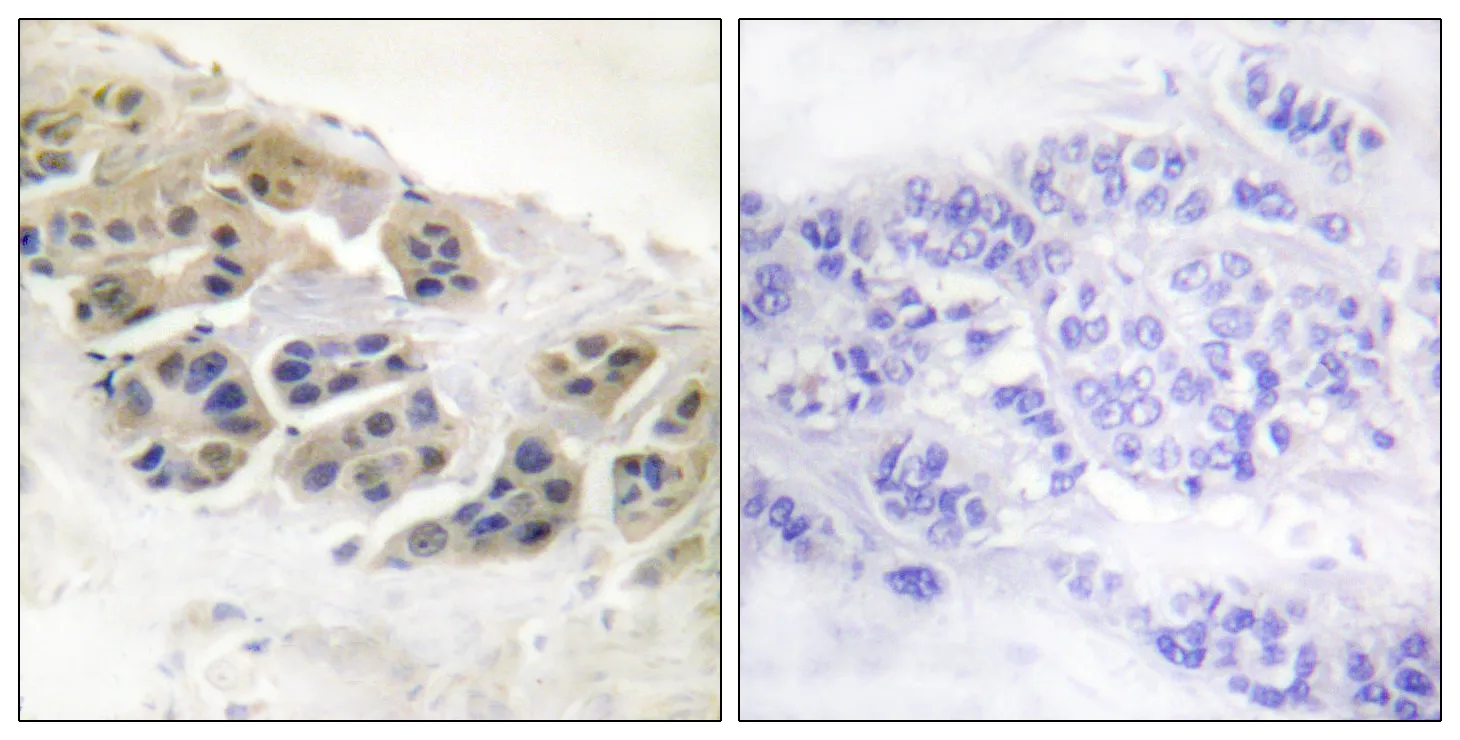

Mammaglobin A Rabbit Polyclonal Antibody

Cat: APRab13614

Size1:50μl Price1:$118

Size2:100μl Price2:$220

Size3:500μl Price3:$980

Size2:100μl Price2:$220

Size3:500μl Price3:$980